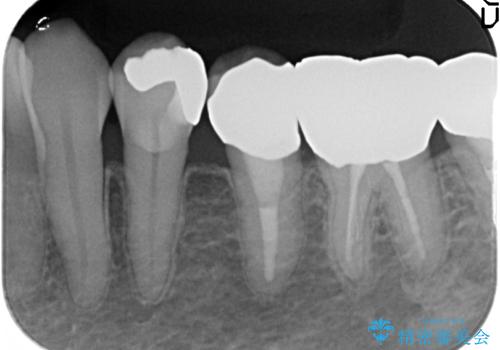

- 左下4番目の歯がなにもしなくてもズキズキ痛むので診て欲しいといらっしゃった方の症例です。

検査の結果、神経の保存は難しかったため、根管治療を行った後オールセラミッククラウンによる補綴を行いました。